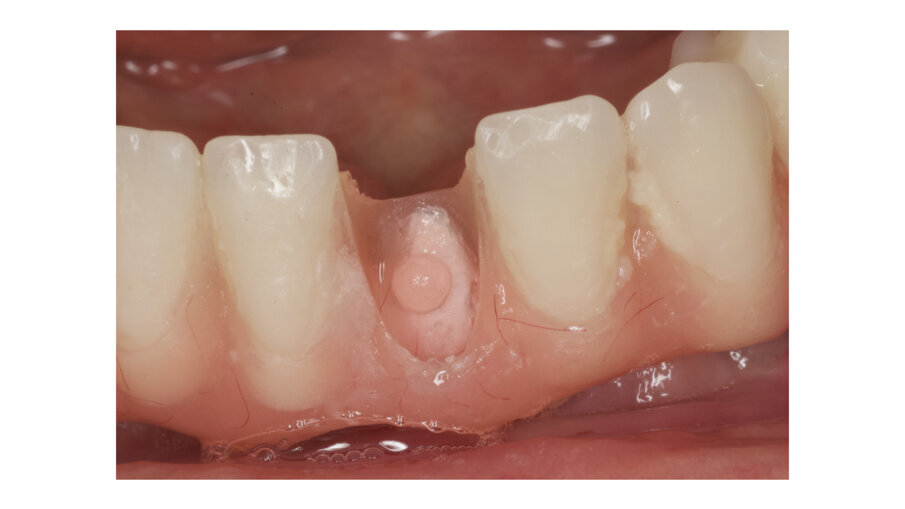

During daily practice, it is very common to face situations where the implant has to be placed lingually due to normal resorption (Fig. 1) of the buccal plate after the extraction. But, at the same time, it is not necessary to perform bone grafting procedures. The result of this scenario is to increase the stress on the implant-bone complex when we use rigid materials like conventional ceramics (Fig. 2). For this daily practice situation, the combination of rigid and resilient materials against the antagonist, allows the stress to the implant-bone complex to be reduced (Figs. 3, 4).

Fig. 1: Implant placed lingually due to the normal resorption of the buccal plate.

Fig. 2: The design of the crown has to be with a pseudo pontic, increasing the oblique load on the crown.